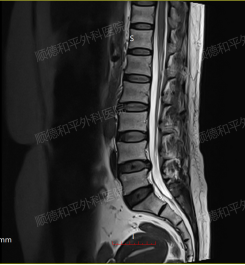

术前&术后

李女士的手术历时2小时,过程顺利。术后当天,她的左下肢放射性麻木疼痛便明显缓解,腰部伤口仅有轻度疼痛,夜间睡眠正常。术后第1天,左下肢轻度胀痛较前显著减轻,已能自如卧床翻身活动,且无下肢麻木及乏力等不适。

得益于精准的术前评估(症状-影像-体征三联验证)与微创技术的合理应用。经皮椎间孔镜技术作为脊柱外科的核心微创术式,尤其适用于单节段椎间盘突出伴神经根性症状的患者。